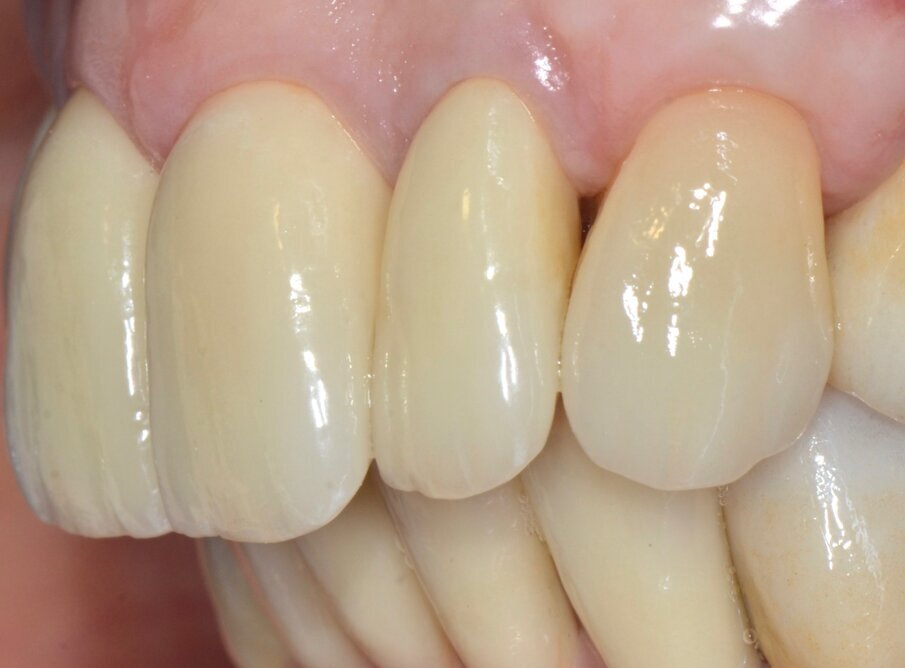

La successiva prova clinica è quella delle ceramiche a biscotto durante la quale viene valutata l’occlusione, la fonetica e l’estetica (Figg. 30-33). Durante la stessa seduta viene eseguita la preparazione per la faccetta in disilicato di litio per il canino superiore sinistro che viene rilevata insieme con l’impronta di rimontaggio delle corone superiori. Una faccetta in resina sul canino viene ribasata e solidarizzata al provvisorio superiore (Figg. 34). La settimana successiva i manufatti finiti vengono provati, cementati adesivamente e vengono eseguite le radiografie finali di controllo (Figg. 35-47).